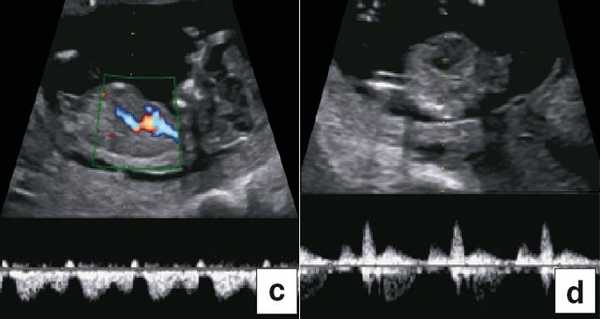

В 90% случаев крупные анеуплоидии у плодов можно обнаружить с помощью комбинированной оценки возраста матери, измерений ТВП и сывороточных маркеров у матери (РАРР-А и свободный бета-ХГЧ) [8]. Результат такого скрининга можно улучшить, исследуя сывороточные маркеры раньше, на сроках от 9 до 10 нед, и проводя УЗИ на 12-й неделе для выявления дополнительных маркеров, таких как носовая кость плода, кровоток в венозном протоке и через трехстворчатый клапан (рис. 5) [9]. Кроме того, выявлять часто встречающиеся хромосомные аномалии у плода позволяет неинвазивное пренатальное тестирование (Non Invasive Prenatal Testing - NIPT).

Рис. 5. Оценка анеуплоидии по ультразвуковым маркерам: толщина воротникового пространства (a), носовая кость (b), венозный проток (c), кровоток через трехстворчатый клапан (d).